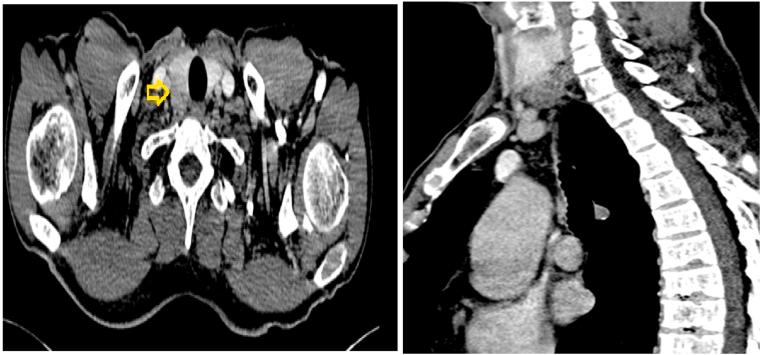

We report a rare case of parathyroid carcinoma in a 61-year-old-male patient who presented with a painless right-sided cervical tumefaction of hard consistency associated with cervical lymphadenopathy. Cervical ultrasonography showed a right parathyroid mass with intimate contact with the homolateral thyroid lobe. A parathyroidectomy enlarged to the adjacent thyroid parenchyma with a selective neck dissection level VI was performed.

我们报告一例罕见的甲状旁腺癌,患者为61岁男性,表现为右侧颈部无痛性坚硬肿块,伴有颈部淋巴结病。颈部超声显示右侧甲状旁腺肿块与同侧甲状腺叶紧密相连。进行了甲状旁腺切除术,扩大至相邻甲状腺实质,并进行了选择性颈部VI区清扫术。